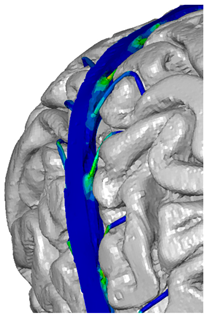

| Frontal veins |  |  |  |

| Parietal veins |  |  | |

| Occipital veins |  |  |